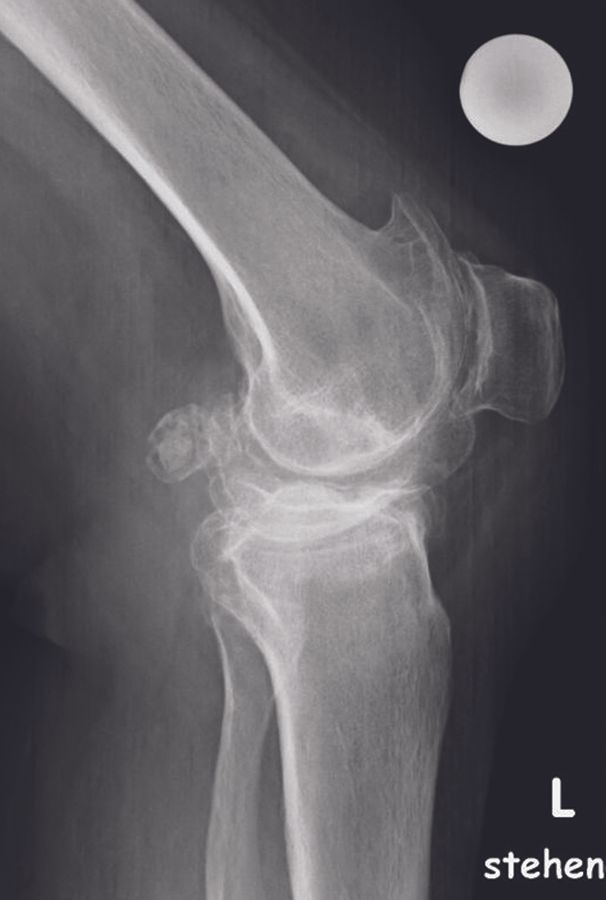

All patients undergo standard anteroposterior and lateral view radiography and a full long leg (hip-knee-ankle angle [HKA]) standing radiograph. The mechanical medial proximal tibia angle (mMPTA) and the mechanical lateral distal femur angle (mLDFA) are evaluated in order to differentiate between osteoarthritis-based varus and bony varus deformity.

Approximately 600 patients were operated in our clinic with the balanced gap technique presented in this paper. In this patient cohort, the HKA changed from -6.7° ± 3.6° (range, -0.5 to -19°) preoperatively to -2.9° ± 2.1° (range, -0.5 to -5.5°) postoperatively. Hence, a residual varus was seen in all patients (Figures 15 - 16).